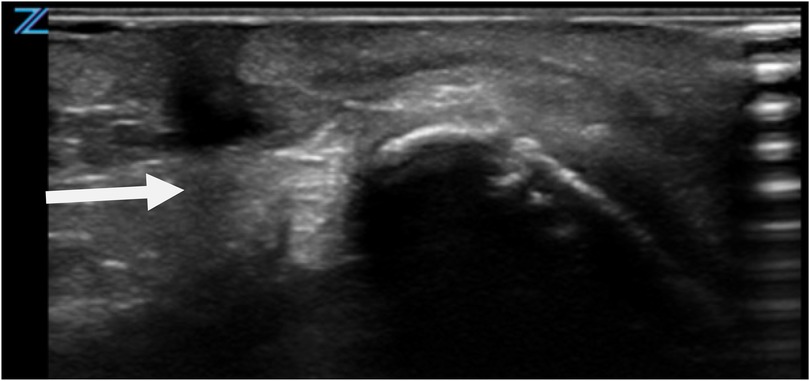

Given the unusual presentation and potential clinical implications, a comprehensive diagnostic evaluation was initiated. Preoperative clinical assessment revealed normal neck mobility, with no restriction of extension or rotation. Ultrasonography served as the primary imaging modality to explore the lesion's depth and its relationship to surrounding structures (Figure 2). The ultrasound revealed a superficial anomaly with no evidence of deep tissue involvement or communication with adjacent anatomical structures. These findings guided a multidisciplinary team—including specialists from pediatric surgery, neonatology, and pediatrics—to proceed with surgical intervention to fully delineate the extent of the malformation and prevent possible complications.

Ultrasound image showing a large heterogeneous hypoechoic region in the neck with irregular margins, indicated by an arrow. The surrounding tissue appears echogenic.

Figure 2. Ultrasonographic evaluation of CMCC. Imaging reveals a blind-ended tract extending caudally, with no evidence of deeper structural involvement.